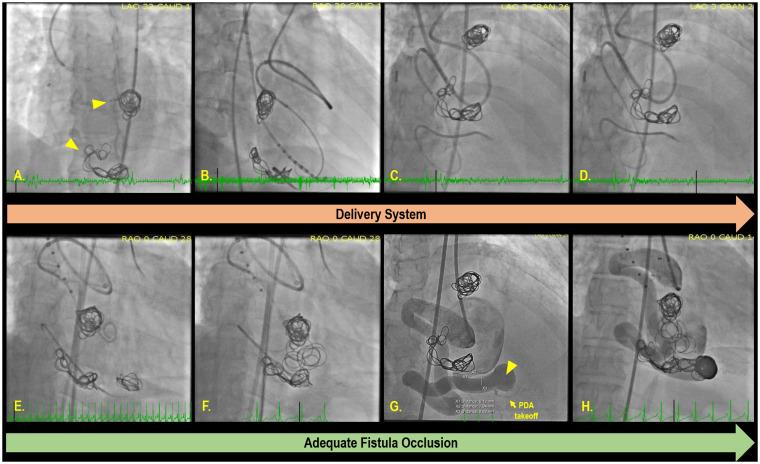

A 51-year-old female with no significant prior history presented with symptoms of dyspnoea and chest discomfort. Extensive evaluation revealed a large CAF between a tortuous right coronary artery (RCA) and the coronary sinus (CS) composed of three aneurysmal pseudochambers. Closure of the RCA-CS fistula was attempted through coil deployment into the fistula neck. However, due to the brisk flow through the fistula, both coils embolized into the fistula sac. An alternative location was subsequently identified on three-dimensional rendering of a computed tomography angiography scan, which revealed a sharp bend in the RCA prior to the fistula neck and distal to the posterior descending artery (PDA) takeoff. Repeat attempt at embolization was accomplished using a telescoping system to reach and occlude the targeted bend. The coil mass remained stable and angiography demonstrated reduced flow through the fistula and preserved patency of the PDA. The decreased residual flow through the fistula secondary to the initial embolization attempt likely aided the successful deployment of coils in the second and final attempt. At 1 year, the patient was doing well with resolution of her symptoms and no clinical symptoms of coronary ischaemia.

We suggest that an initial unsuccessful attempt at transcatheter embolization of a CAF should not preclude subsequent attempts for closure when there exists an appropriate indication.